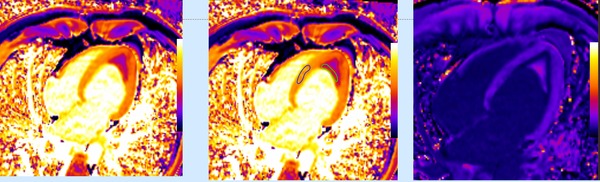

Combined CMR and PET/CT give synergistic information in patients with granulomatous cardiomyopathy